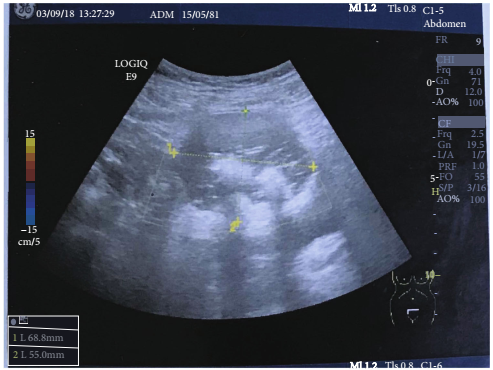

53岁女性患者,G3P3,无特殊病史,在过去6年中处于更年期,因腹部体积增大,盆腔疼痛持续4个月就诊。体检和妇科检查发现右腹壁有一可触及的疼痛肿块。超声图像显示存在盆腔肿块,其特征为皮样卵巢囊肿(图1)。盆腔磁共振成像(MRI)显示一个圆形、边界清晰的右卵巢肿块,位于子宫上,肿瘤内有脂肪样信号,提示为成熟的囊性畸胎瘤。肿瘤标志物在正常范围内,癌抗原125(CA125)为13.1 UI/mL,CA 19-9为20 UI/mL。

图1. 盆腔肿块大小约为68x55mm,表现为卵巢皮样囊肿,回声不均匀,内部回声高